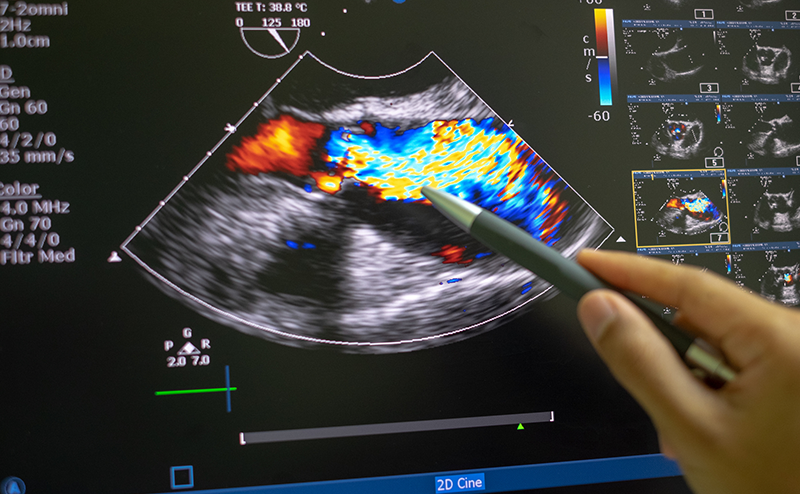

The right ventricular systolic pressure (RVSP) determined by echocardiography can approximate the pulmonary artery systolic pressure (assuming a normal pulmonic valve). Determining this value is predicated on the ability to measure the velocity of the tricuspid regurgitant jet in an apical four chamber view. To obtain this value, the tricuspid regurgitant jet is first identified in an apical four chamber view (A4C) using color doppler. The eccentric jet shown in Figure 1 highlights the importance of first localizing it with color doppler. Then a continuous wave (CW) doppler line is placed through that jet with the focal zone (diamond) in or near the vena contracta (the thinnest part of the jet close to the valve). The resulting wave form should demonstrate repeating downward parabolas. (Figure 1) Increasing the doppler scale, and adjusting the baseline upwards, may be necessary to avoid aliasing for these high velocity cases. The pressure gradient is then extrapolated by using a simplified Bernoulli equation. In the case of this patient, the velocity measures 5.53 m/s, so the pressure gradient (PG) is about 122mmHg (normal would be zero to trace regurgitation). In cases where the diagnosis of PAH is known, comparing the patient’s historic RVSP value to that on presentation, can be helpful.

Figure 1. Continuous wave doppler measuring the maximum velocity of the tricuspid regurgitant jet (TR Vmax).